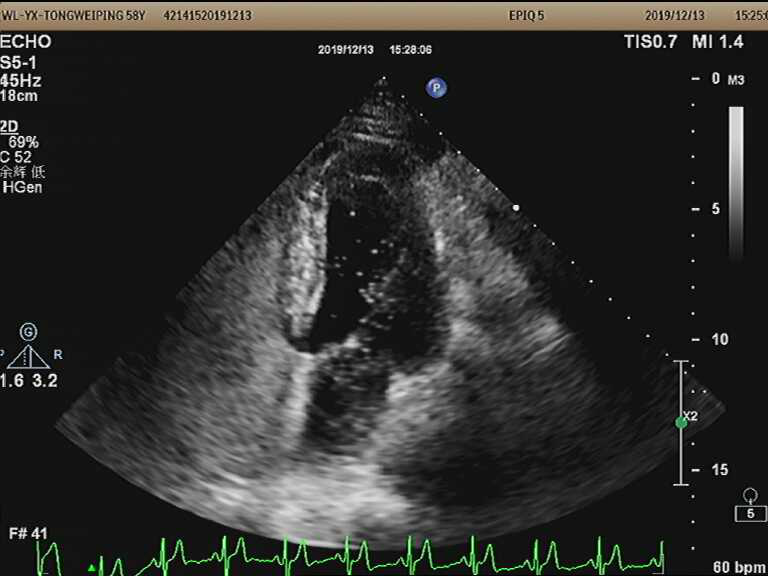

图片1.png

图一:未见明显经典卵圆孔未闭的“搭错样”声像图改变

仅见“细线样”房间隔回声

图一、图二高度怀疑卵圆孔未闭,结合临床表现(如不明原因头疼、青年人群的腔梗),建议经食管超声心动图和右心声学造影,下图为此患者诊断卵圆孔未闭提供了进一步的依据(右心声学造影见右向左大量微气泡)